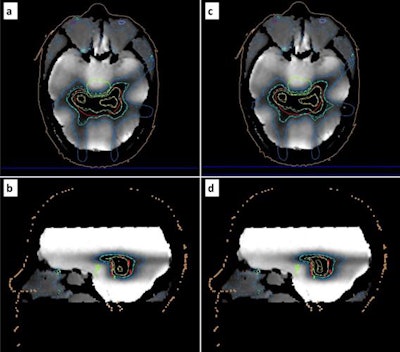

To test their approach, Pappas and collaborators created a seven-beam IMRT plan for a hypothetical C-shaped brain lesion partly surrounding the brainstem (the organ at risk). They placed each phantom on the Elekta Unity MR-linac's treatment couch and acquired MR images. The treatment planning system calculated the required virtual couch shifts and created an adapted treatment plan, using the adapt-to-position strategy. Finally, they delivered the adapted plan to each respective phantom.

Prior to the gel measurements, the researchers evaluated the dose response characteristics of the gel under irradiation and readout conditions and saw a linear response in the investigated dose range. Immediately after plan delivery, they MR scanned the phantom to read out the dosimetry gel. Measurements corresponded well with the adapted and original calculated dose distributions. Dose volume histograms were in excellent agreement with calculations for the planning target volume (PTV), though minor discrepancies were seen for organs at risk.

The team also calculated several relative dose volume metrics for the PTV. These confirmed the good agreement (within ± 4%) between adapted and delivered plans. For this specific case and adaptation method, no considerable discrepancies were detected between the adapted and original plans.